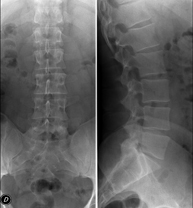

- Lumbar spine X-ray

This technique uses X-ray rendered imaging to examine the lumbar spine. Indicated for: sciatica, trauma, lower back pain.